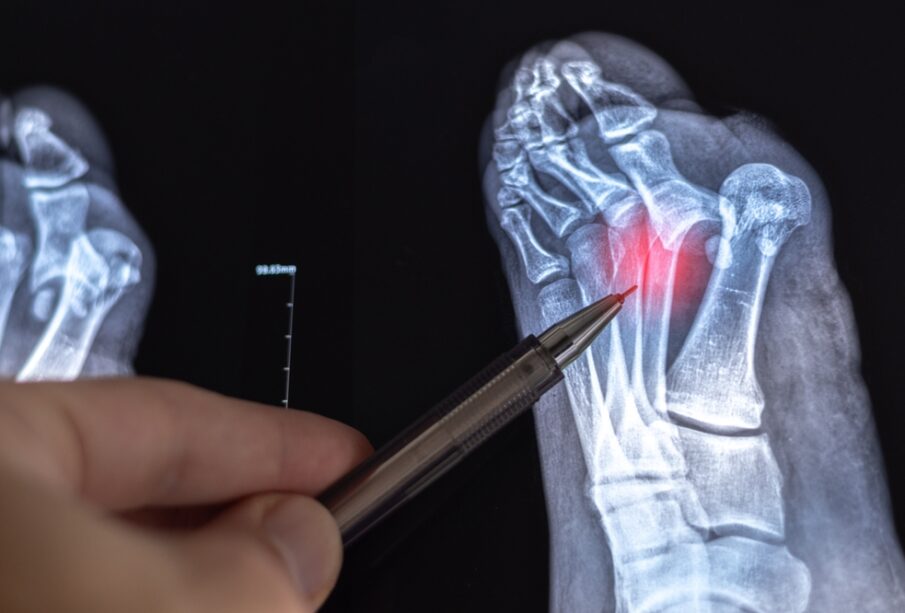

Η ανοικτή ανάταξη κατάγματος με εσωτερική οστεοσύνθεση είναι μια χειρουργική τεχνική της ορθοπαιδικής, που χρησιμοποιείται για να σταθεροποιούνται και να πωρώνονται πιο σύνθετα κατάγματα.

Η συγκεκριμένη μέθοδος βασίζεται σε δύο βασικά στάδια. Στην ανοικτή ανάταξη, ο χειρουργός προσεγγίζει χειρουργικά την περιοχή της κάκωσης και επαναφέρει με χειρισμούς τα σπασμένα άκρα του οστού στη σωστή ανατομική θέση. Στη συνέχεια ακολουθεί η εσωτερική οστεοσύνθεση, δηλαδή η τοποθέτηση ειδικών ιατρικών εμφυτευμάτων μέσα ή γύρω από το οστό, ώστε το κάταγμα να παραμείνει ακίνητο και σταθερό κατά την επούλωση. Για τον σκοπό αυτό μπορούν να χρησιμοποιηθούν πλάκες, βίδες, καρφίδες ή ράβδοι, ανάλογα με το οστό που έχει υποστεί κάταγμα και τον τύπο του τραυματισμού.